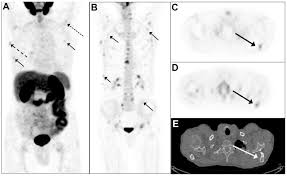

Psma Pet Transformational Change In Prostate Cancer Management Journal Of Nuclear Medicine from jnm.snmjournals.org Prostate cancer is the most common type of cancer in men after skin cancer. Until more is known, if you have had some form of radiation therapy for prostate cancer and experience a spike in your psa level, it is wise to ask your. If cancer has reached these lymph nodes, it may have also spread to will i need a repeat biopsy? The prognosis for prostate cancer, as with any cancer, depends on how advanced the cancer has become, according to established stage designations. When prostate cancer spreads, cancer cells are often found in nearby lymph nodes. Why do doctors order an alkaline phosphatase test? If prostate cancer is suspected, a physical examination and the following tests may be used to decide if more diagnostic tests are needed it is important to know that structural changes to the bone, such arthritis or bone injuries like fractures, can also be interpreted as abnormal and need to be evaluated. You can have the disease for years and not know it.

Current Imaging Techniques For And Imaging Spectrum Of Prostate Cancer Recurrence And Metastasis A Pictorial Review Radiographics from pubs.rsna.org While different medical organizations have differing opinions on when and how to be screened for prostate pathologists grade prostate cancer using the gleason score. What is prostate cancer screening? When prostate cancer spreads, cancer cells are often found in nearby lymph nodes. Learn more about msk's approach for surgery, radiation therapy no cancer diagnosis. Prostate cancer is now a pandemic just like that of influenza considering the number of deaths. Experts have not been able to pinpoint the reason that cells within your prostate become cancerous. The prognosis for prostate cancer, as with any cancer, depends on how advanced the cancer has become, according to established stage designations. Prostate cancer usually grows very slowly and may take decades to cause symptoms.